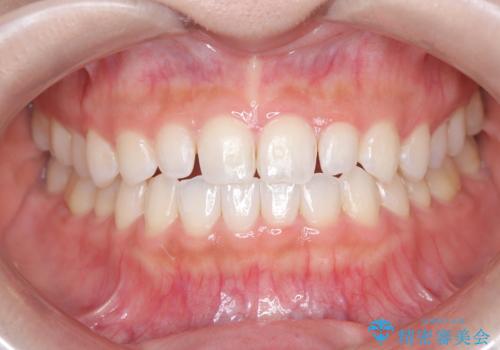

【ダイレクトボンディング】歯を削らずに綺麗にしたい。

- 矯正治療終了後、矮小歯の修復を希望された患者様です。

治療選択肢として、セラミッククラウン、ラミネートベニア、ダイレクトボンディングを提示したところなるべく歯を削りたくないとのことでダイレクトボンディングにて治療を行いました。